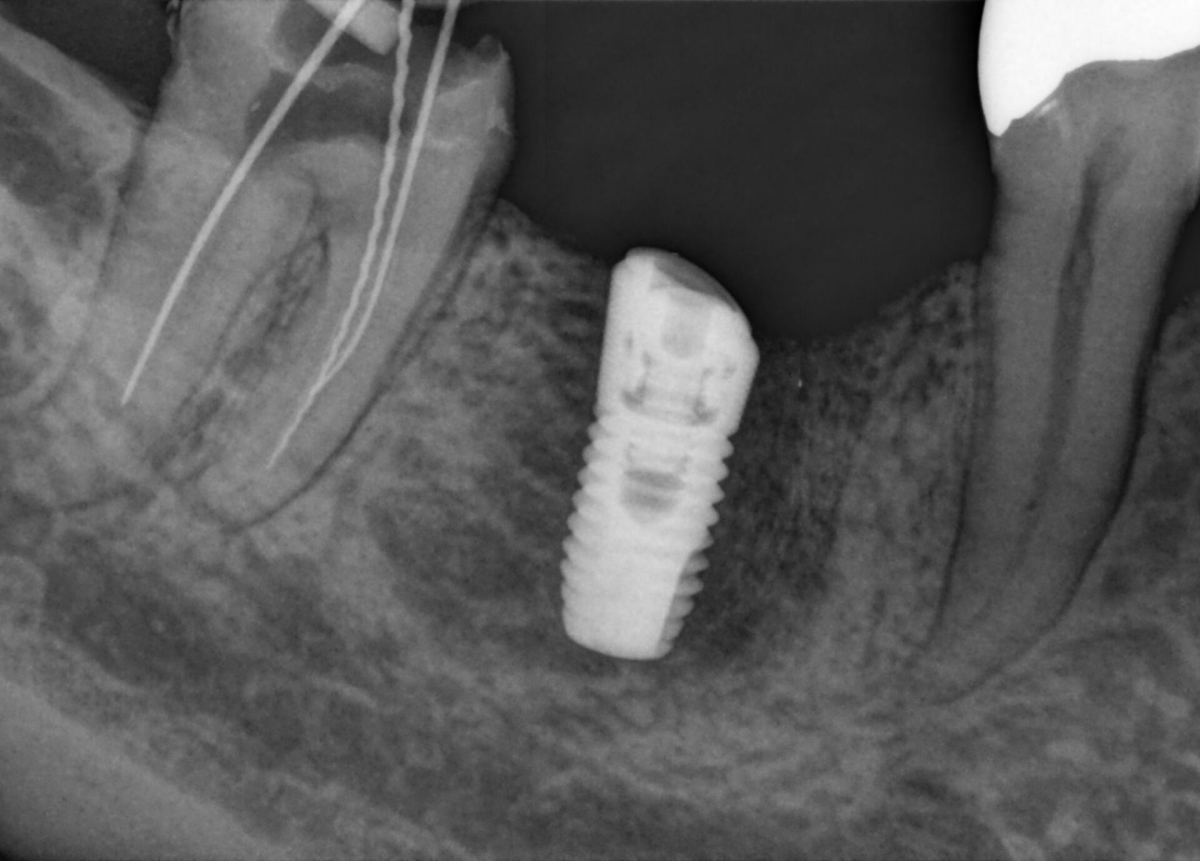

Imágenes superiores para cuidado óptimo del paciente

Los sensores intraorales de Dentsply Sirona proporcionan calidad de imagen de vanguardia que apoya el diagnóstico preciso del tratamiento y visión clara de la situación clínica. Respaldado por elecciones expansivas del sistema, mejora de filtro de imagen y servicio de vanguardia y personal de apoyo, los sensores intraorales Xios ofrecen varias posibilidades para su consultorio - brindándole beneficio a usted y sus pacientes.